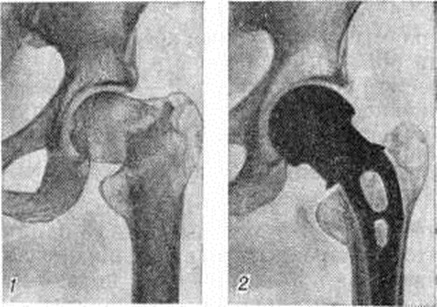

При выборе метода лечения Переломы (особенно оперативного) важно выяснить адаптационно-компенсаторные возможности и резервные силы организма. Пожилым ослабленным больным предпочтительно применять простые, легко переносимые и сравнительно безопасные приёмы лечения. Следует избегать методов лечения, вынуждающих длительно лежать в постели и затрудняющих передвижение. У данного контингента больных значительно возрастает степень операционного риска. Поэтому оперативное вмешательство по поводу Переломы у пожилых людей нужно применять тогда, когда консервативные методы не эффективны, а также в тех случаях, когда оперативный способ может быть легче перенесён больным, чем консервативный. Оперативное лечение наиболее часто применяют при аддукционных (варусных) медиальных Переломы шейки бедренной кости. В этих случаях показан остеосинтез трёхлопастным гвоздём или другим фиксатором, а также эндопротезирование (рисунок 12 и 13). При соответствующих показаниях вертельные и диафизарные Переломы бедра также лечат оперативно.